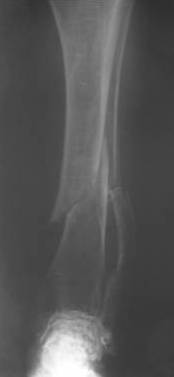

Уважаемые коллеги! Здравствуйте! Прошу у Вас совета вот по какому случаю.В нашу клинику поступила женщина 71 год. Травма в результате ДТП. (Пациентка передвигалась на инвалидной каляске и была сбита автомобилем). Диагноз: Множественная травма. Перелом нижней трети правого бедра. Перелом средней трети правой б/берцовой, малоберцовой кости, нижней трети левой большоберцовой, м/берцовой кости.Травматический шок. Со стороны внутренних органов и систем без патологии. Больная госпитализирована в реанимационное отделение, где было наложено двойное скелетное вытяжение за правую н/конечность. Левая н/конечность иммобилизована гипсовой лонгетой. Из анамнеза: больная является инвалидом 1 группы по опорно-двигательному аппарату. В детстве перенесла рахит. Осложнением которого "О" образная деформация нижних конечностей. Ограничено отведение нижних конечностей, деформирующий артроз тазобедренных и коленных суставов. В 1990 году перелом правого бедра остеосинтез пластиной. После операции больная передвигалась только на костылях или в инвалидной коляске.

Прошу прощения за качество снимков. Р-графия производилась в реанимационном отделении передвижным аппаратом.

Но даже при малоинвазивной методике лечения применимой для даной больной существуют следующие проблемы: выраженный остеопороз, тонкий кортикал, очень широкий канал.

Проблема в том, что в сагитальной плоскости угол голеней =30 градусам. Ширина канала 30.